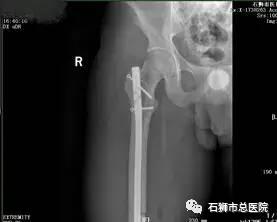

股骨骨折

股骨粗隆间粉碎性骨折